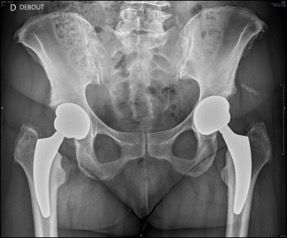

Hips in coxa vara sometimes present a very significant femoral offset which may be prove to be difficult to restore using standard stems. In this case, a varus-tilted or lateralized stem should be used and this will require a very low femoral cut, often with loss of residual femoral offset and a risk of lengthening the lower limb. Positioning a straight cementless stem in varus runs the risk of trajectory error and femoral pain. If a modular neck implant is chosen, the increased lever arm results in significant pressures on the modular neck and neck-head junction with risks that are already known. Finally, even with a cemented stem, positioning it in varus will increase the pressures on the bone-cement interface, with a risk of early loosening. With calcar-guided short stems, the stem will follow the medial cortex of the neck (which will have been cut high), naturally finding a varus tilt and making it possible to reproduce even very significant offsets (Figs 4 and 5).

In total hip replacement, there is often a relative reduction in the acetabular offset due to burring off a few millimetres, which is necessary for the implant to fit in the hip socket cavity, and this is compensated for by a relative increase in femoral offset, to restore the overall hip offset.

In the specific case of marked dysplasia of the hip socket where there is insufficient bone coverage, slightly firmer burring may be required to obtain optimal fixation of the hip socket implant. In this case, the rotation centre will be displaced medially, and the loss of acetabular offset must be compensated for on the femoral side in order to restore the anatomy and reduce the risk of instability. This is perhaps one of the limitations of the use of these stems aligning with the calcar femorale. This is because, in these dysplasia cases, coxa valga is the default morphotype. A calcar-guided stem will in this case spontaneously find a valgus positioning with a femoral offset that will be difficult to increase to compensate for the loss of overall offset. Use of a long head risks lengthening the limb again rather than increasing femoral offset.